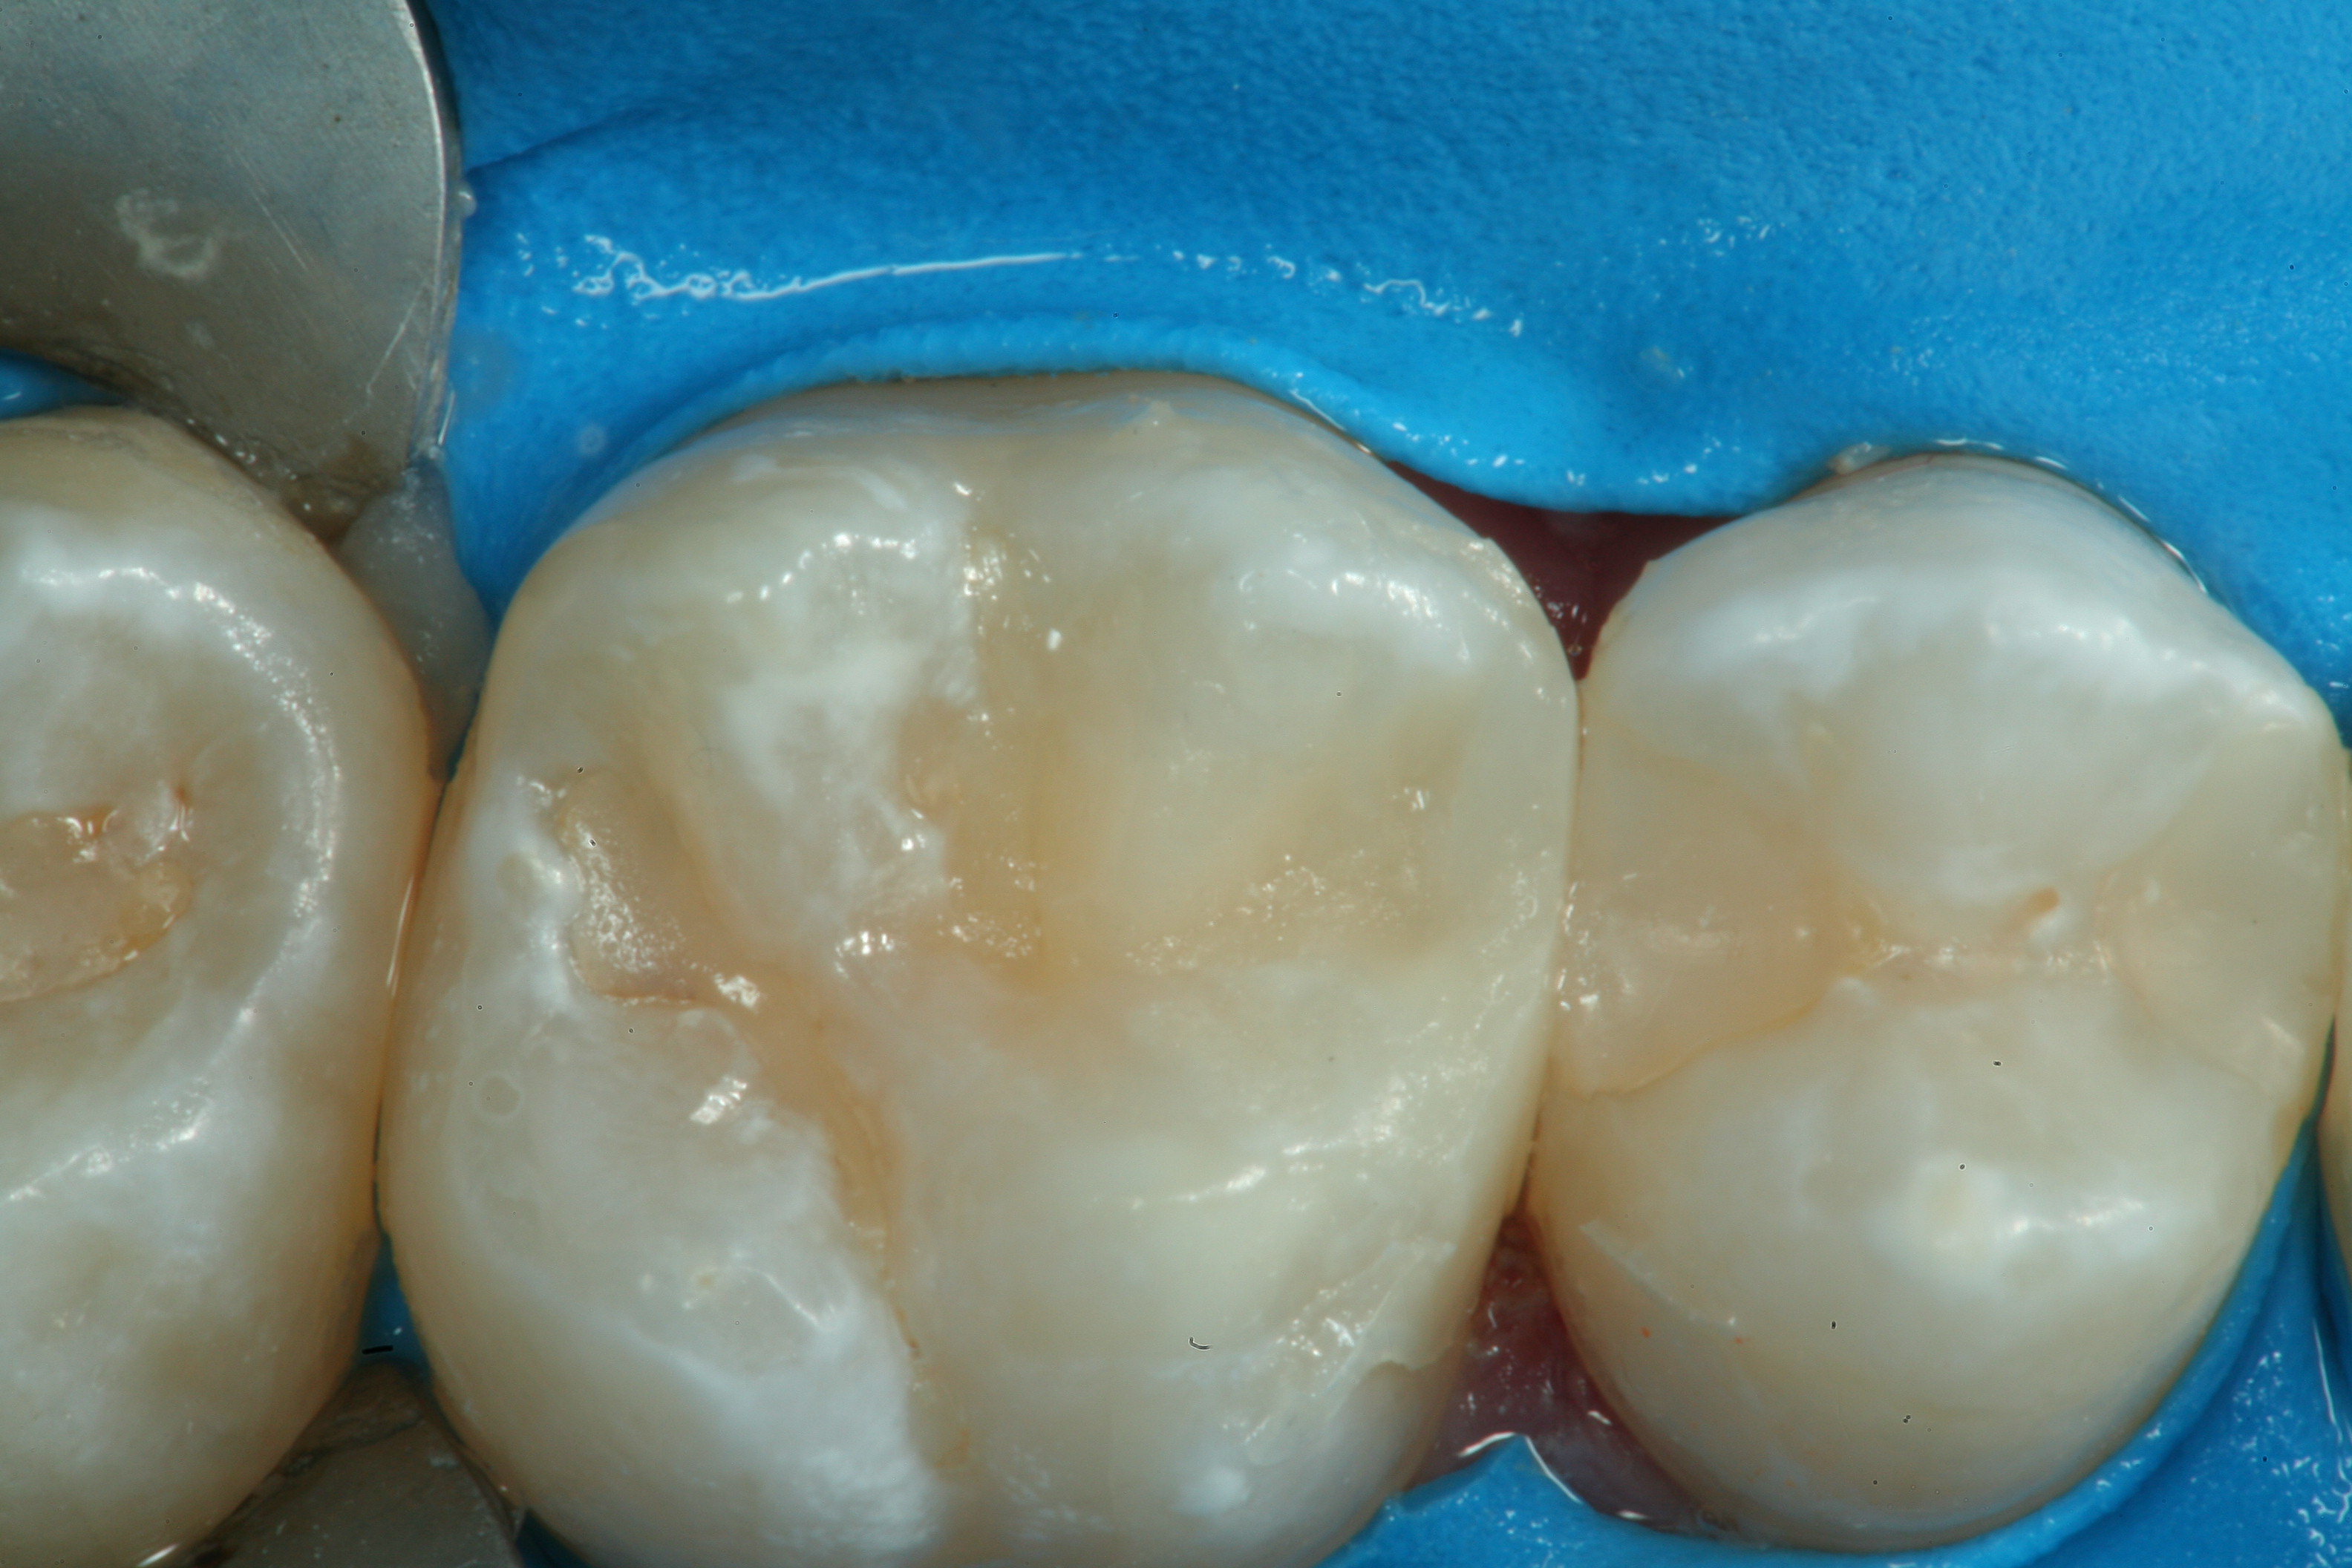

Fig 20. A distal-occlusal cavity preparation in tooth No. 29 and a mesial-occlusal-distal cavity preparation in tooth No. 30 are both shown from the occlusal aspect. A diode laser has been used interproximally to create supragingival margins to aid in precise gingival placement of the restorative material.

Figure 20